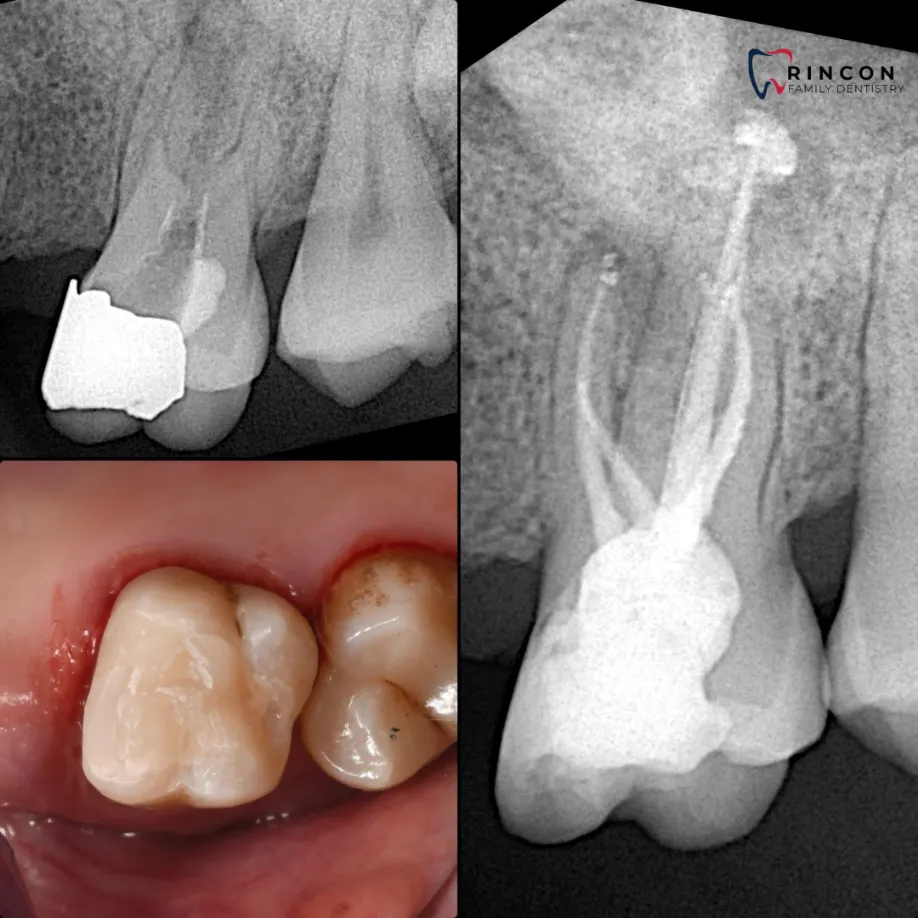

Periapical X-rays

If sharp pain or swelling appears near a specific tooth, a periapical scan helps identify decay, infection, or bone loss. It captures the full tooth from crown to root, offering a complete picture of its condition. Our advanced digital sensors deliver crisp results in seconds while keeping exposure low.

X-ray of Tooth Decay

If you have noticed dark spots or sensitivity after eating, dental X-rays can pinpoint early signs of decay before they cause pain. We use high-resolution intraoral scans that show the structure of your teeth and gums clearly, so treatment can start on time.